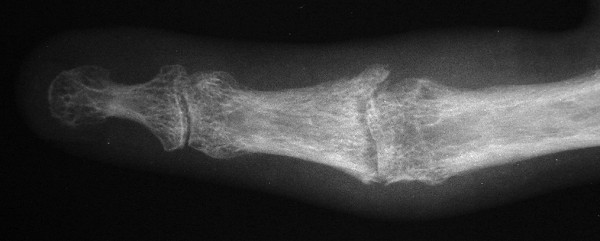

This gentleman presented with stiffness and lateral deviation of the ring finger proximal interphalangeal joint following volar plate arthroplasty for dorsal fracture dislocation.

Preoperative and postoperative radiographs.